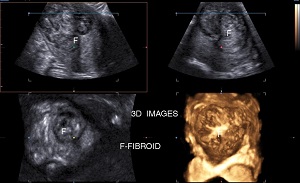

• Fibroids are benign tumours developing in or around uterus. These tumours are made up of muscle & fibrous tissue. They vary in size,position, echogenicity, composition & vascularity .

• Symptoms: Excessive periods, repeated bleeding per vagina, pelvic pain, feeling of lump, infertility or may be asymptomatic. Sonography can show location, size, number, vascularity, degenerative changes & its relation with endometrium. It can also diagnose obstruction of ureters by fibroids.